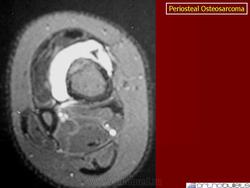

Рентгенологическая картина выявляет очаг поражения на поверхности кости. Очаговые фокусы кальциноза, формирование спикул, нечеткая граница опухолевого узла, мягкотканный компонент, отсутствие поражения медуллярного отдела кости, все названные рентгенологические признаки характерны для периостальной остеосаркомы. Для выявления характера поражения костномозгового канала проводится дополнительное исследование с применением КТ и МТР.

Макроскопическая картина при периостальной остеосаркоме складывается из фокусов дольчатой, преимущественно хрящевидной, белесоватой опухолевой ткани на поверхности кортикальной пластинки кости без внедрения в костномозговой канал.

Микроскопическая картина при периостальной остеосаркоме имеет признаки хондробластического варианта остеосаркомы, но не обладает специфичностью. Характерно дольчатое строение, хондроидная дифференцировка клеток, умеренная степень атипии ядер опухолевых клеток.